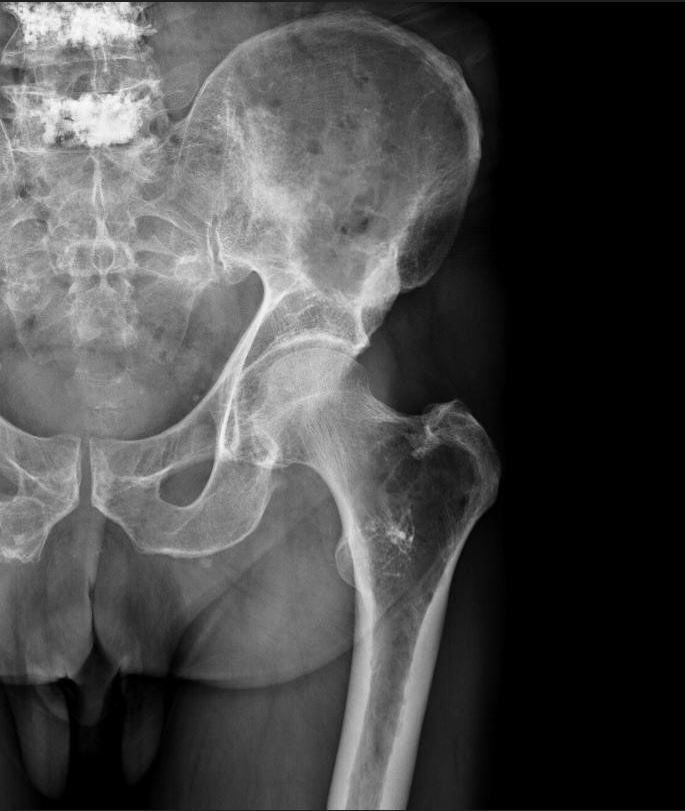

Le Centre Hospitalier de Versailles comporte plusieurs services prenant en charge des tumeurs cancéreuses (Oncologie, Hématologie, Urologie, Gynécologie, Chirurgie digestive, ORL et Maxillo-faciale). Au cours de l’évolution de leur pathologie, ces patients peuvent voir apparaitre des lésions osseuses secondaires à leur cancer initial. Ces lésions peuvent entrainer une fragilisation osseuse avec un risque de fracture ou une fracture avérée, des douleurs osseuses ou articulaires ou des troubles neurologiques en cas d’atteinte de la colonne vertébrale.

La prise en charge de ces lésions varie selon le type de tumeur, son stade d’évolution, l’efficacité prévisible des traitements disponibles. En cas de nécessité d’un traitement chirurgical des membres, ce dernier est en règle réalisé par l’équipe du Service d’Orthopédie de Versailles en liaison avec l’équipe en charge de la prise en charge de la tumeur initiale et après la réalisation d’une Réunion de Concertation Pluridisciplinaire (RCP) pour planifier l’ensemble des étapes du traitement. En cas de nécessité d’un traitement interventionnel non chirurgical (radiologie interventionnelle, radiothérapie) ou en cas d’intervention sur la colonne vertébrale, celui-ci se fera en dehors du Centre Hospitalier de Versailles, avec des équipes spécialisées partenaires toujours après une RCP.

Fragilisation osseuse du col fémoral gauche sur un myélome : aspect radiographique. Patient déjà traité en radiologie interventionnelle par cimentoplastie des vertèbres L4 et L5.

Fragilisation osseuse du col fémoral gauche sur un myélome : aspect au scanner confirmant la fracture partielle de la lésion.

Traitement par clou cervico-céphalique permettant le maintien de la marche et la disparition des douleurs. Poursuite du traitement général du myélome ayant obtenu la rémission.